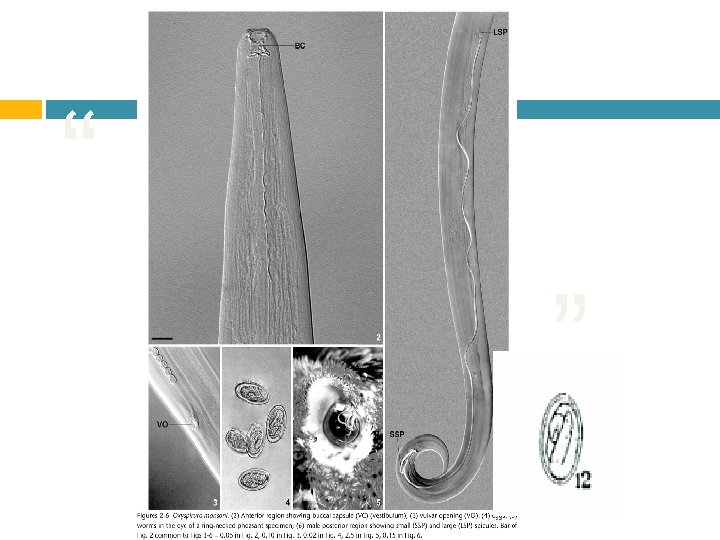

Etiologia: Oxyspirura mansoni Oxyspirura parvorum Oxyspirura petrowi

Localizacion: • Membrana nictitante • Conducto nasolagrima l • Sacos conjuntivos

Patogenia: A. Irritativa A. Inflamatori a A. Traumati ca